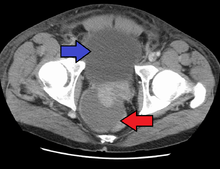

Antibiotics are the first line of treatment in acute prostatitis (Cat. I). Antibiotics usually resolve acute prostatitis infections in a very short time, however a minimum of two to four weeks of therapy is recommended to eradicate the offending organism completely.[4] Appropriate antibiotics should be used, based on the microbe causing the infection. Some antibiotics have very poor penetration of the prostatic capsule, others, such as Ciprofloxacin, Co-trimoxazole and tetracyclines such as doxycycline penetrate well. In acute prostatitis, penetration of the prostate is not as important as for category II because the intense inflammation disrupts the prostate-blood barrier. It is more important to choose a bacteriocidal antibiotic (kills bacteria, e.g. quinolone) rather than a bacteriostatic antibiotic (slows bacterial growth, e.g. tetracycline) for acute potentially life-threatening infections.[5] Severely ill patients may need hospitalization, while nontoxic patients can be treated at home with bed rest, analgesics, stool softeners, and hydration. Patients in urinary retention are best managed with a suprapubic catheter or intermittent catheterization. Lack of clinical response to antibiotics should raise the suspicion of an abscess and prompt an imaging study such as a transrectal ultrasound (TRUS).[6]